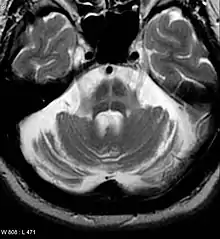

An MRI finding that is seen commonly in Multiple System atrophy. This occurs on the Pons.

Hot Cross Bun sign that is commonly found in MRI of multiple system atrophy